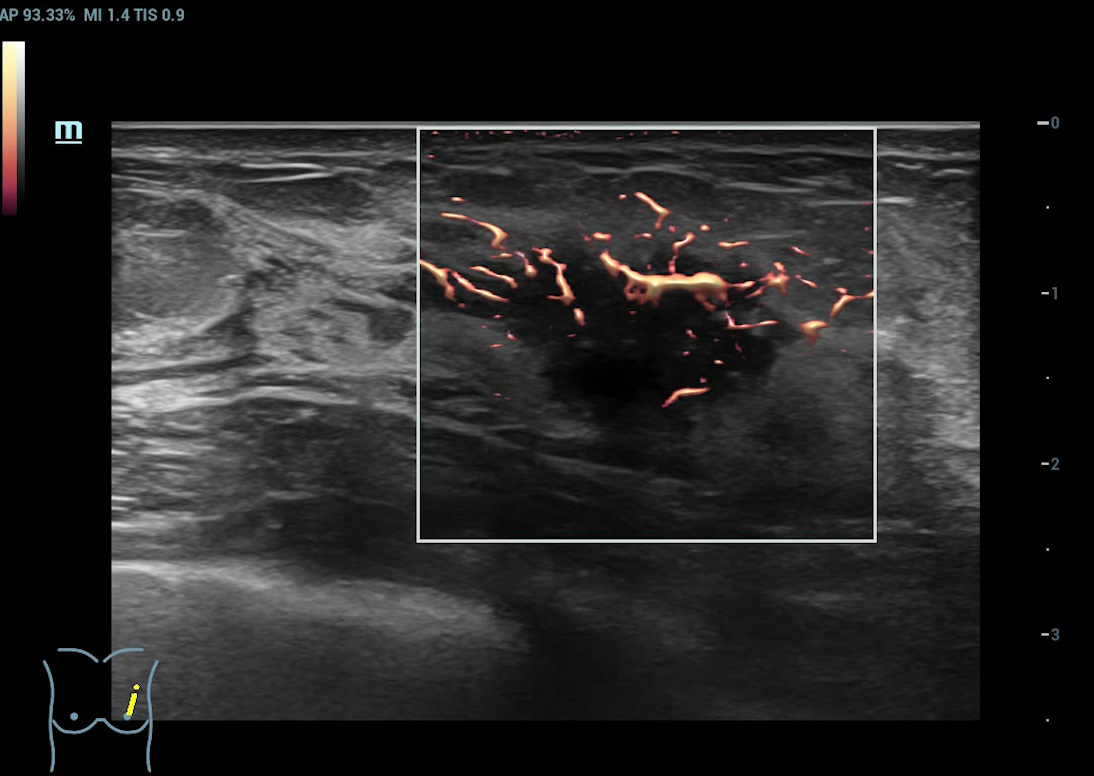

Ultra Micro Angiography (UMA)

UMA migliora la sicurezza diagnostica ampliando la visibilitĂ dei flussi sanguigni fino al livello dei vasi piĂč piccoli, con una sensibilitĂ e una risoluzione superiori.

Massa mammaria pUMA

Massa mammaria cUMA

Massa mammaria